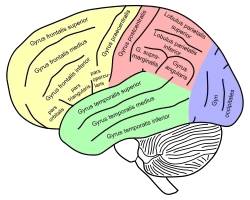

Lateral surface of left cerebral hemisphere, viewed from the side. (Inferior temporal gyrus shown in orange.) | |

Basal view of a human brain Lateral view of a human brain, main gyri labeled.

Lateral view of a human brain, main gyri labeled. Cerebrum. Lateral view. Deep dissection. Inferior temporal gyrus labeled at bottom center.